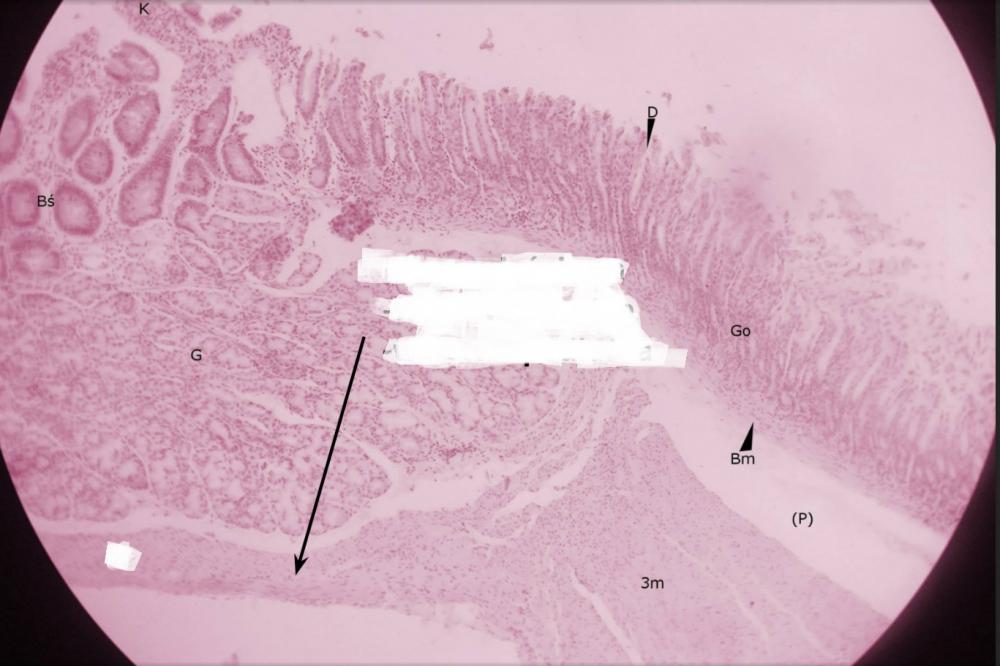

dołki żołądkowe (przejście żołądka w dwunastnicę)

pólka żołądkowe (przejście żołądka w dwunastnicę)

rozgałęzione gruczoły cewkowe - odźwiernikowe (przejście żołądka w dwunastnicę)

kosmek jelitowy (przejście żołądka w dwunastnicę)

krypta jelitowa (przejście żołądka w dwunastnicę)

gruczoły Brunnera (przejście żołądka w dwunastnicę)

błona mięśniowa, składająca się z warstwy okrężnej o podłużnej (przejście żołądka w dwunastnicę)

miejsce po błonie podśluzowej (przejście żołądka w dwunastnicę)

blaszka mięśniowa błony śluzowej (przejście żołądka w dwunastnicę)

gruba, trójwarstwowa mięśniówka żołądka (przejście żołądka w dwunastnicę)